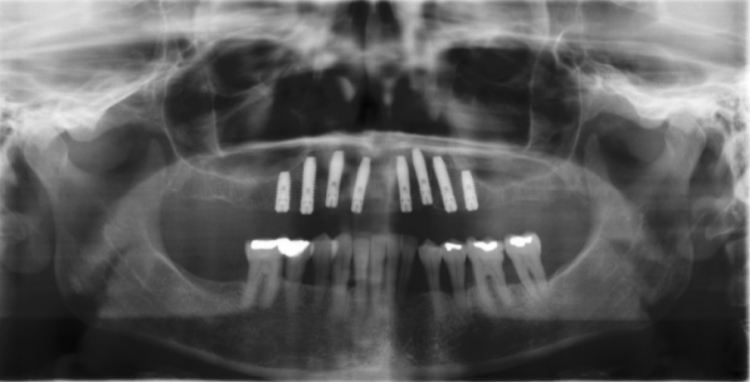

One of my fields of expertise is implantology. After successfully completing a structured 3-year advanced training course at the German Society of Implantology, I graduated as a specialist for dental implants.

Implants have established themselves as the most durabledental prosthesis - they help not only to create a beautiful smile and aesthetics but also to improve the quality of life. An implant takes the function of a tooth root and forms the pillar for the dentures. It is invisible in the jaw and firmly anchored. For the implants only pure titan material is used, since this material has a high body tolerance and no allergies are known. One of the greatest advantages is that the healthy teeth don't need to be grinded down to fix a bridge or a removable prosthesis. With implants the patient doesn't feel any difference to his natural teeth.

Dental implants are as close to the original condition as no other restoration. The new tooth roots inteosseograte after implantation. The implanted screw serves as the foundation for single tooth crowns or bridges. Prostheses can also be securely fixed using implants. They do not have any restrictions in everyday life, such as laughing, talking or chewing.